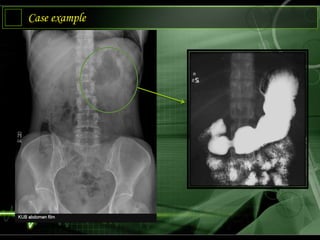

Case example

Artificial Contrast

1) Use contrast

media

2) Changes subject

contrast

3) Changes

radiographic (film

contrast)